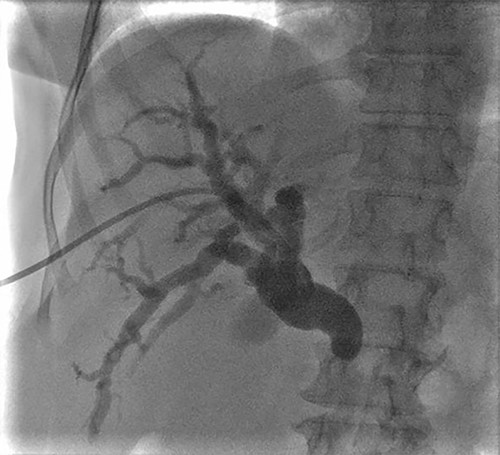

A 57-year-old Caucasian woman presented with a 2-week history of mild abdominal pain, jaundice, generalized pruritus, stool discoloration and dark urine. She had deranged liver function tests with total bilirubin 30.5 mg/dl alkaline phosphatase 729 U/l, SGOT 222 U/l, SGPT 291 U/l and γ-GT 837 U/l. The tumor marker Ca19–9 was within normal limits. Imaging revealed intrahepatic and extrahepatic bile duct dilatation with abnormal tapering at the distal end of common bile duct, without evidence of calculi or dilatation of pancreatic duct (Fig. 1). The patient had an unsuccessful ERCP due to difficult cannulation, which was followed by percutaneous transhepatic cholangiography (PTC) with external stent insertion to decompress biliary system. Brushing cytology was inconclusive (Fig. 2). Based on these findings, a diagnosis of distal cholangiocarcinoma was suspected. Further staging did not reveal any metastatic disease. The patient underwent Whipple’s procedure without any complications and was discharged on post-operative day 16 in a very good condition.

PTC showing dilation of intrahepatic biliary tree with abnormal tapering in the mid bile duct and lack of contrast filling distally.